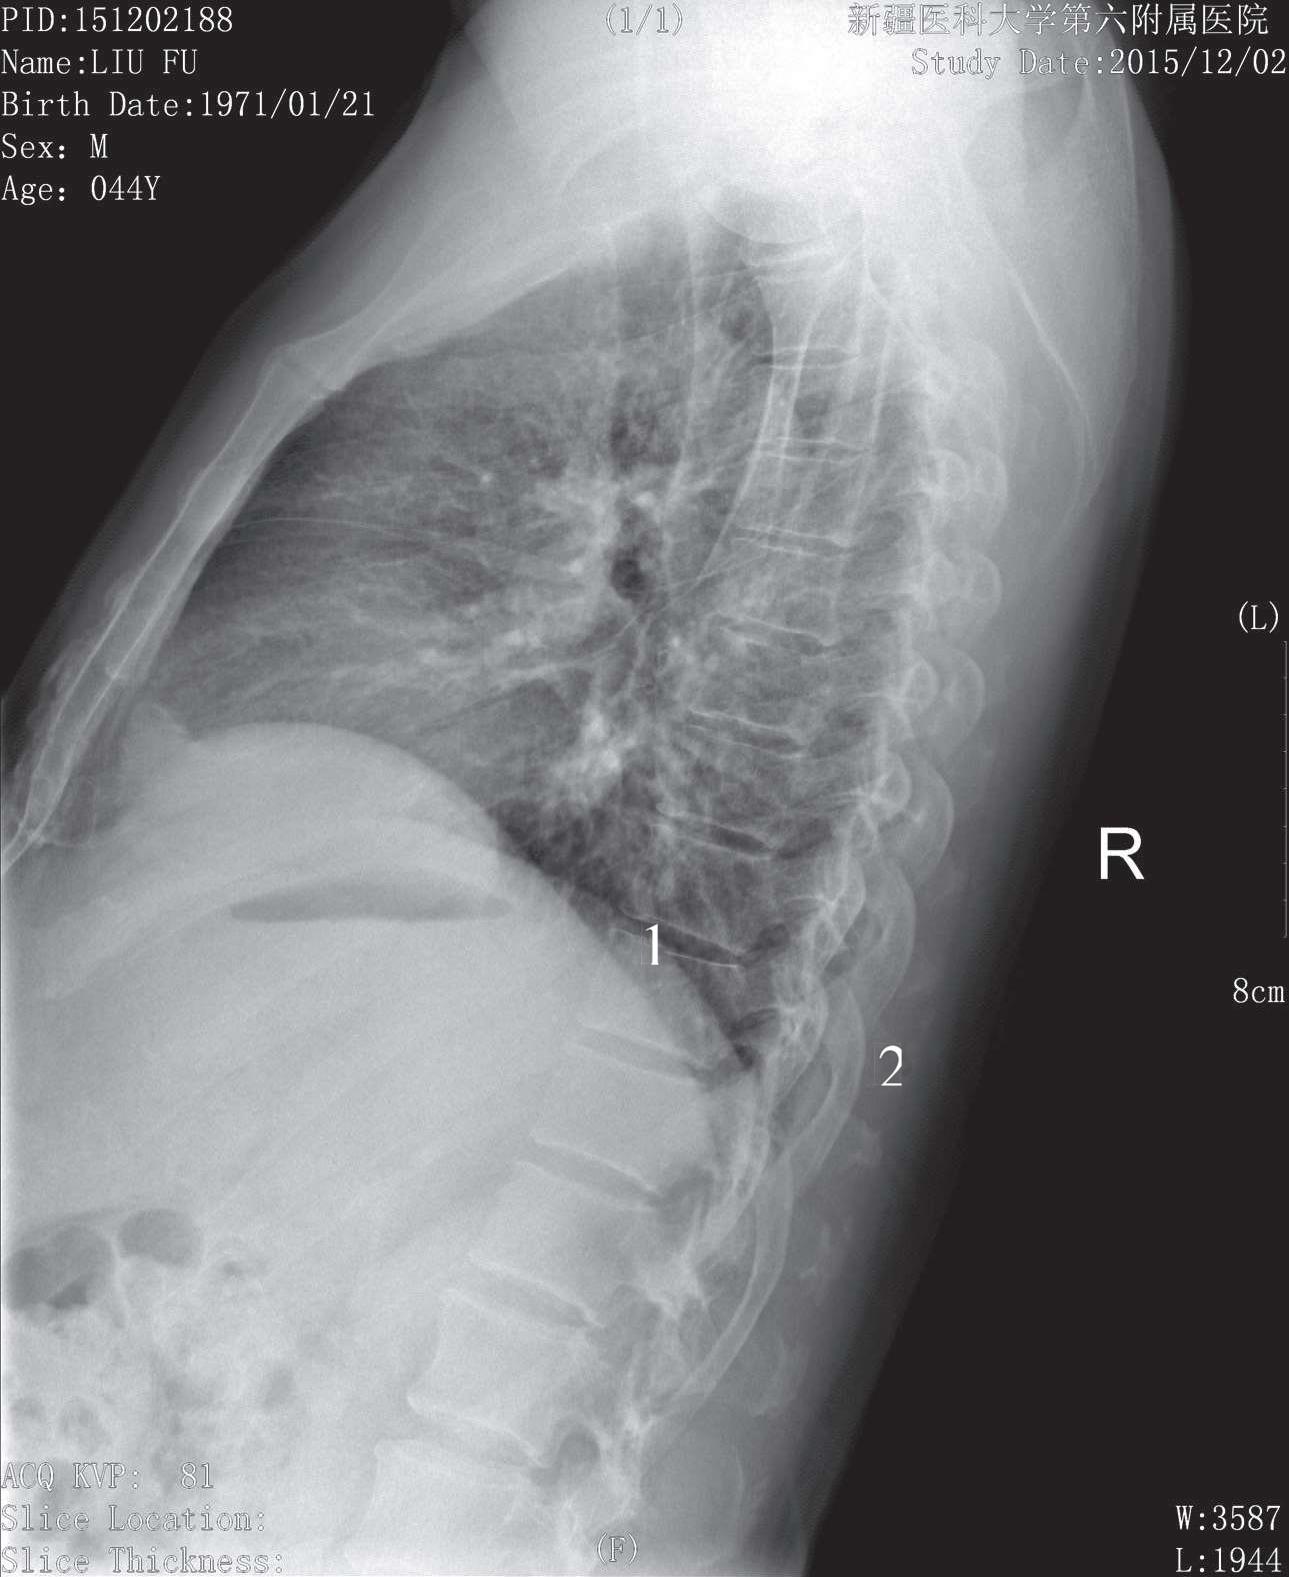

被检者侧卧于检查床上,两臂上举屈曲,头枕于臂上,双下肢屈曲以避免身体晃动,身体冠状面与床面垂直,腰部用棉垫垫平,膝间放一沙袋,脊柱纵轴与检查床中线一致,影像接收器上缘平C 7 ,下缘包括L 1 ,中心线对准T 7 椎体垂直射入。影像显示T 3 ~T 12 侧位像于照片正中,所示胸椎连贯成一生理性后凸的自然弧线,椎体为四方形,椎间隙显示清晰并优于正位片,棘突较长,斜向后下方,其余椎体附件结构亦显示清晰(图3-12)。

1. 椎间隙; 2. 棘突

图3-12 胸椎侧位片